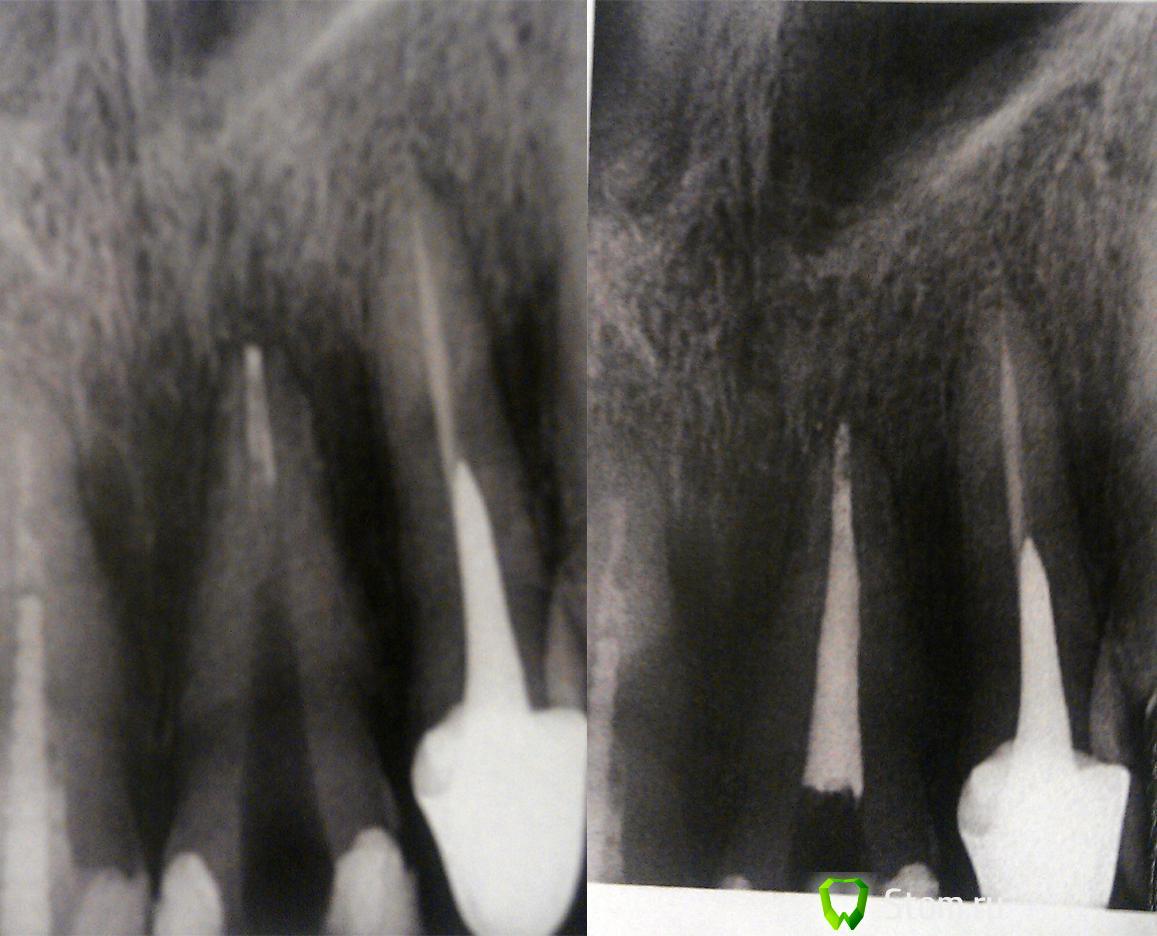

sagitta Опубликовано 8 февраля, 2012 Поделиться Опубликовано 8 февраля, 2012 Здравствуйте! С наступлением холодов заболел передний (21) зуб, на котором уже была обширная пломба. Зуб реагировал на холод, боль была умеренная. Обратилась к стоматологу, доктор сказал, что надо депульпировать, что и было сделано. Далее врач положил в канал крезофен и отпустил походить с лекарством несколько дней. Тут началось самое интересное, боль усилилась, к ночи терпеть уже не было сил, на следующий день я обратилась повторно, врач сделал снимок, сказал, что в канале все хорошо и велел принимать "нимесил" до следующего запланированного приема. Боль немного утихла, но при накусовании и к вечеру усиливалась. В день приема ситуация немного улучшилась и после очередных снимков было принято решение пломбировать канал. После этого два дня я буквально на стену лезла, спасали только обезболивающие. На следующем приеме доктор распломбировал канал и положил в него каласепт и метапекс и отпустил гулять две недели. Все это время зуб продолжал болеть и болел до тех пор пока не вытащили эти пасты. Далее канал снова был запломбирован и я снова отправилась гулять на пару дней. После поставили постоянную пломбу, но чувствительность зуба осталась. Иногда боль при накусывании и поднывание ближе к ночи. После постановки постоянной пломбы прошло два дня. Снимки у меня на руках есть только с предпоследнего посещения, их прилагаю. Еще есть выписка из карты с описанием всего лечения, но написано от руки и почерк я не везде могу разобрать. И, собственно, вопрос, в чем тут дело? Почему зуб продолжает болеть, если канал пролечен хорошо? Ссылка на комментарий

ger_berra Опубликовано 8 февраля, 2012 Поделиться Опубликовано 8 февраля, 2012 Ещё снимок делайте с запломбированными каналами.И ответьте,пожалуйста,на следующие вопросы(по возможности):1.Во время лечения коффердам использовался?(это резиновая тряпочка на рамке,одевается на зуб во время лечения)2.Если коффердама не было,то закрывали ли Вы рот в процессе лечения?3.Из шприца в канал раствор наливали?Он должен пахнуть хлоркой.4.Временная пломба была сначала мягкая,а потом затвердела или сразу твёрдая?5.Чем пломбировали канал? Ссылка на комментарий